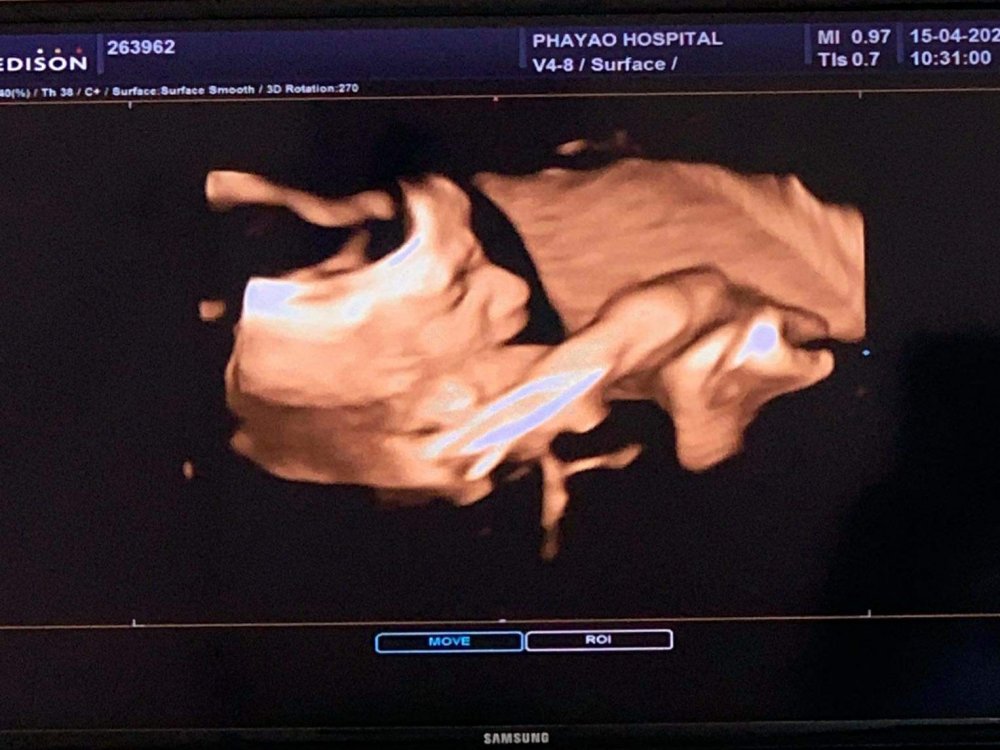

ฝากครรภ์ครั้งนี้ แฟนตั้งใจว่าจะอัลตร้าซาวด์ 4 มิติ เพื่อจะได้เห็นหน้าลูกสาวตัวน้อยเป็นครั้งแรก หลังจากที่เตะท้องแม่อยู่หลายสัปดาห์ โดยการอัลตร้าซาวด์ 4 มิติ นี้ หลักการคือ การถ่ายภาพแล้วนำมาเรียงต่อกันให้เป็นภาพเคลื่อนไหว โดยใช้คลื่นเสียง ซึ่งภาพที่จะปรากฎก็จะเป็นภาพแบบ Real Time ครับ โดยอายุครรภ์ที่เหมาะสม ที่สามารถเริ่มซาวด์ได้ก็ตั้งแต่สัปดาห์ที่ 19 ของการตั้งครรภ์ เป็นต้นไปครับ

ข้อดีของการซาวด์ 4 มิติ คือ จะสามารถเห็นอวัยวะ , เพศลูก , โครงสร้างใบหน้า , กระดูกสันหลัง , พัฒนาการในครรภ์ และอื่น ๆ

แต่ว่าช่วงที่ไปลูกนอนอยู่พอดี จึงขยับตัวน้อย มีหาวบ้าง เอานิ้วมาดูดบ้าง เรียกได้ว่าการมาซาวด์ ก็ต้องอาศัยโชคในระดับหนึ่งเหมือนการซาวด์ปกตินั่นแหละ แต่ได้เห็นเพียงเท่านี้ รู้ว่าลูกร่างกายแข็งแรงสมบูรณ์ ครบ 32 ก็เป็นความสุขของคนเป็นพ่อเป็นแม่แล้วใช่ไหมละครับ